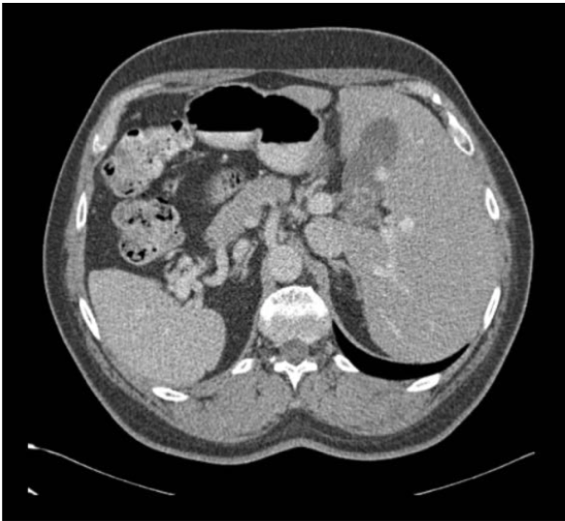

全球每年因癌症死亡的人数中,肝癌患者占据了很大的比例。根据最新的2018年全球癌症统计数据,肝癌患者的人数在所有新增癌症患者中占比排名第六,肝癌的死亡人数在所有癌症死亡人数中占比排名第四。放射科医师和肿瘤学家通过分析肝脏区域的CT图像(如图1-1所示),来研究肝脏组织的大小、形状和纹理异常,从而进行肝脏肿瘤的诊断和治疗。

图1-1 肝脏区域CT图像